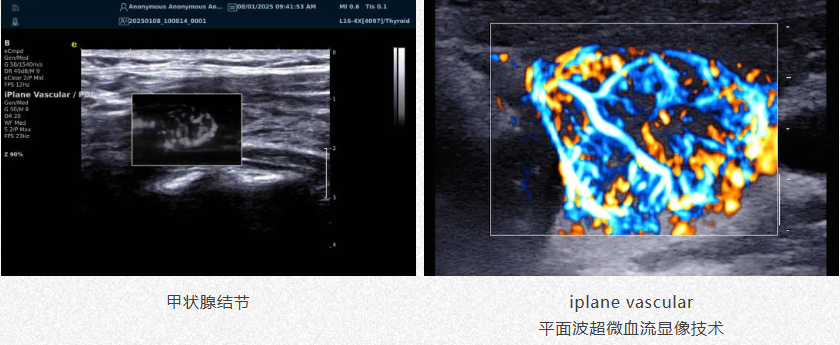

精准描绘微血管世界

iPlane Vascular

平面波超微细血流显像技术

肿瘤良恶性鉴别

1.高效检测出肿瘤微细血管与低速血流,帮助医生早期发现肿瘤并进行良恶性的鉴别诊断。

2.通过血管指数(VI)定量评估肿瘤内部血管,为诊断提供客观依据。